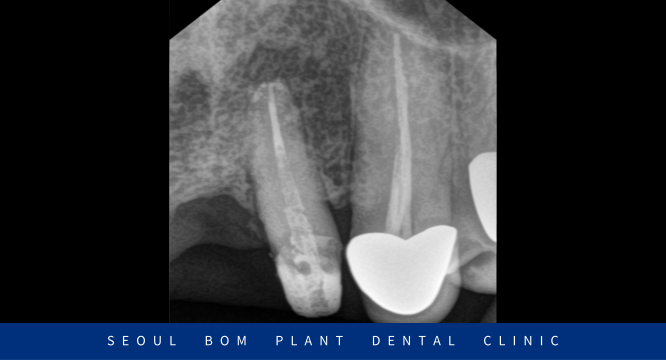

먼저 구강 내를  확인해 보았더니

위턱의 앞니가 오른쪽 두 번째 앞니(#12)부터

왼쪽 두 번째 앞니(#22)까지 총 4개의 보철물로 이루어진 브릿지 상태로

구강 위생 관리 부족으로 인해 잇몸 퇴축이 심하였으며,

외상으로 인한 충격으로 양측 첫 번째 앞니(#11,21) 사이가

파절되어 뒤틀려 있는 것으로 보였는데요.

발치를 하기에는 아깝다고 판단되어

신경치료를 통해 치아를 보존하는 치료를 진행하기로 하였습니다.

감염된 신경조직을 제거한 뒤 깨끗하게 소독하는 과정을 거쳤으며

환자분께서 별다른 증상이나 통증이 없으신 것을 확인한 뒤

신경을 제거한 근관내부에 치과재료로 치근 끝까지

꼼꼼하게 채워 넣으면서 신경치료를 마무리하였는데요.